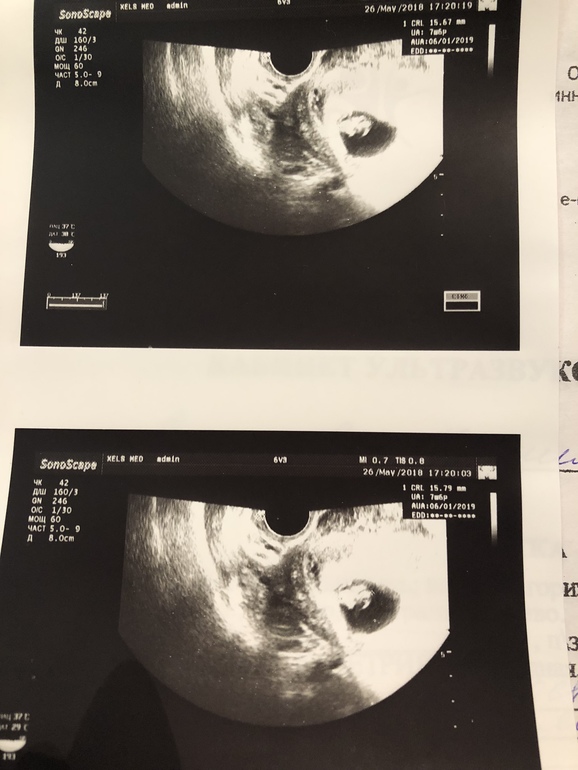

Встретиться с врачём мы договорились через 2 недели - посмотреть уже эмбрион и послушать сердечко 😍😍😍.

Через 2 недели я полетела на третье свидание с малышом! И он меня не разачаровал ! Пульсировало сердечко и маааленький червячек виднелся там, где ещё недавно было пусто)) Беременность соответствовала 7 неделям, 6 дням.

Тут я немного выдохнула и позволила себе чуть расслабиться. Зашла то я уже дальше, чем с прошлой ЗБ. Тогда не появился эмбрион даже ☹️.